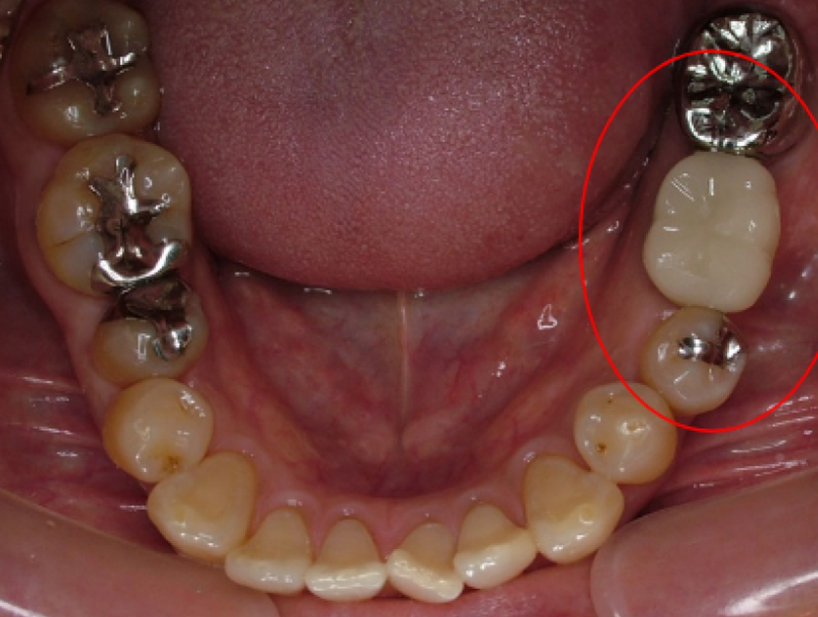

治療前治療後

| 治療内容 | インプラント奥歯1本・根管治療・矯正治療(圧下) |

|---|---|

| 患者様の年齢 | 40歳 |

| 患者様の性別 | 男性 |

| 治療期間 | 1年 |

| 治療回数 | 矯正治療合わせて50回程度 |

| 治療費用 | 根管治療1歯6万円/インプラント治療1歯50万円 矯正治療:1歯 10万円 |